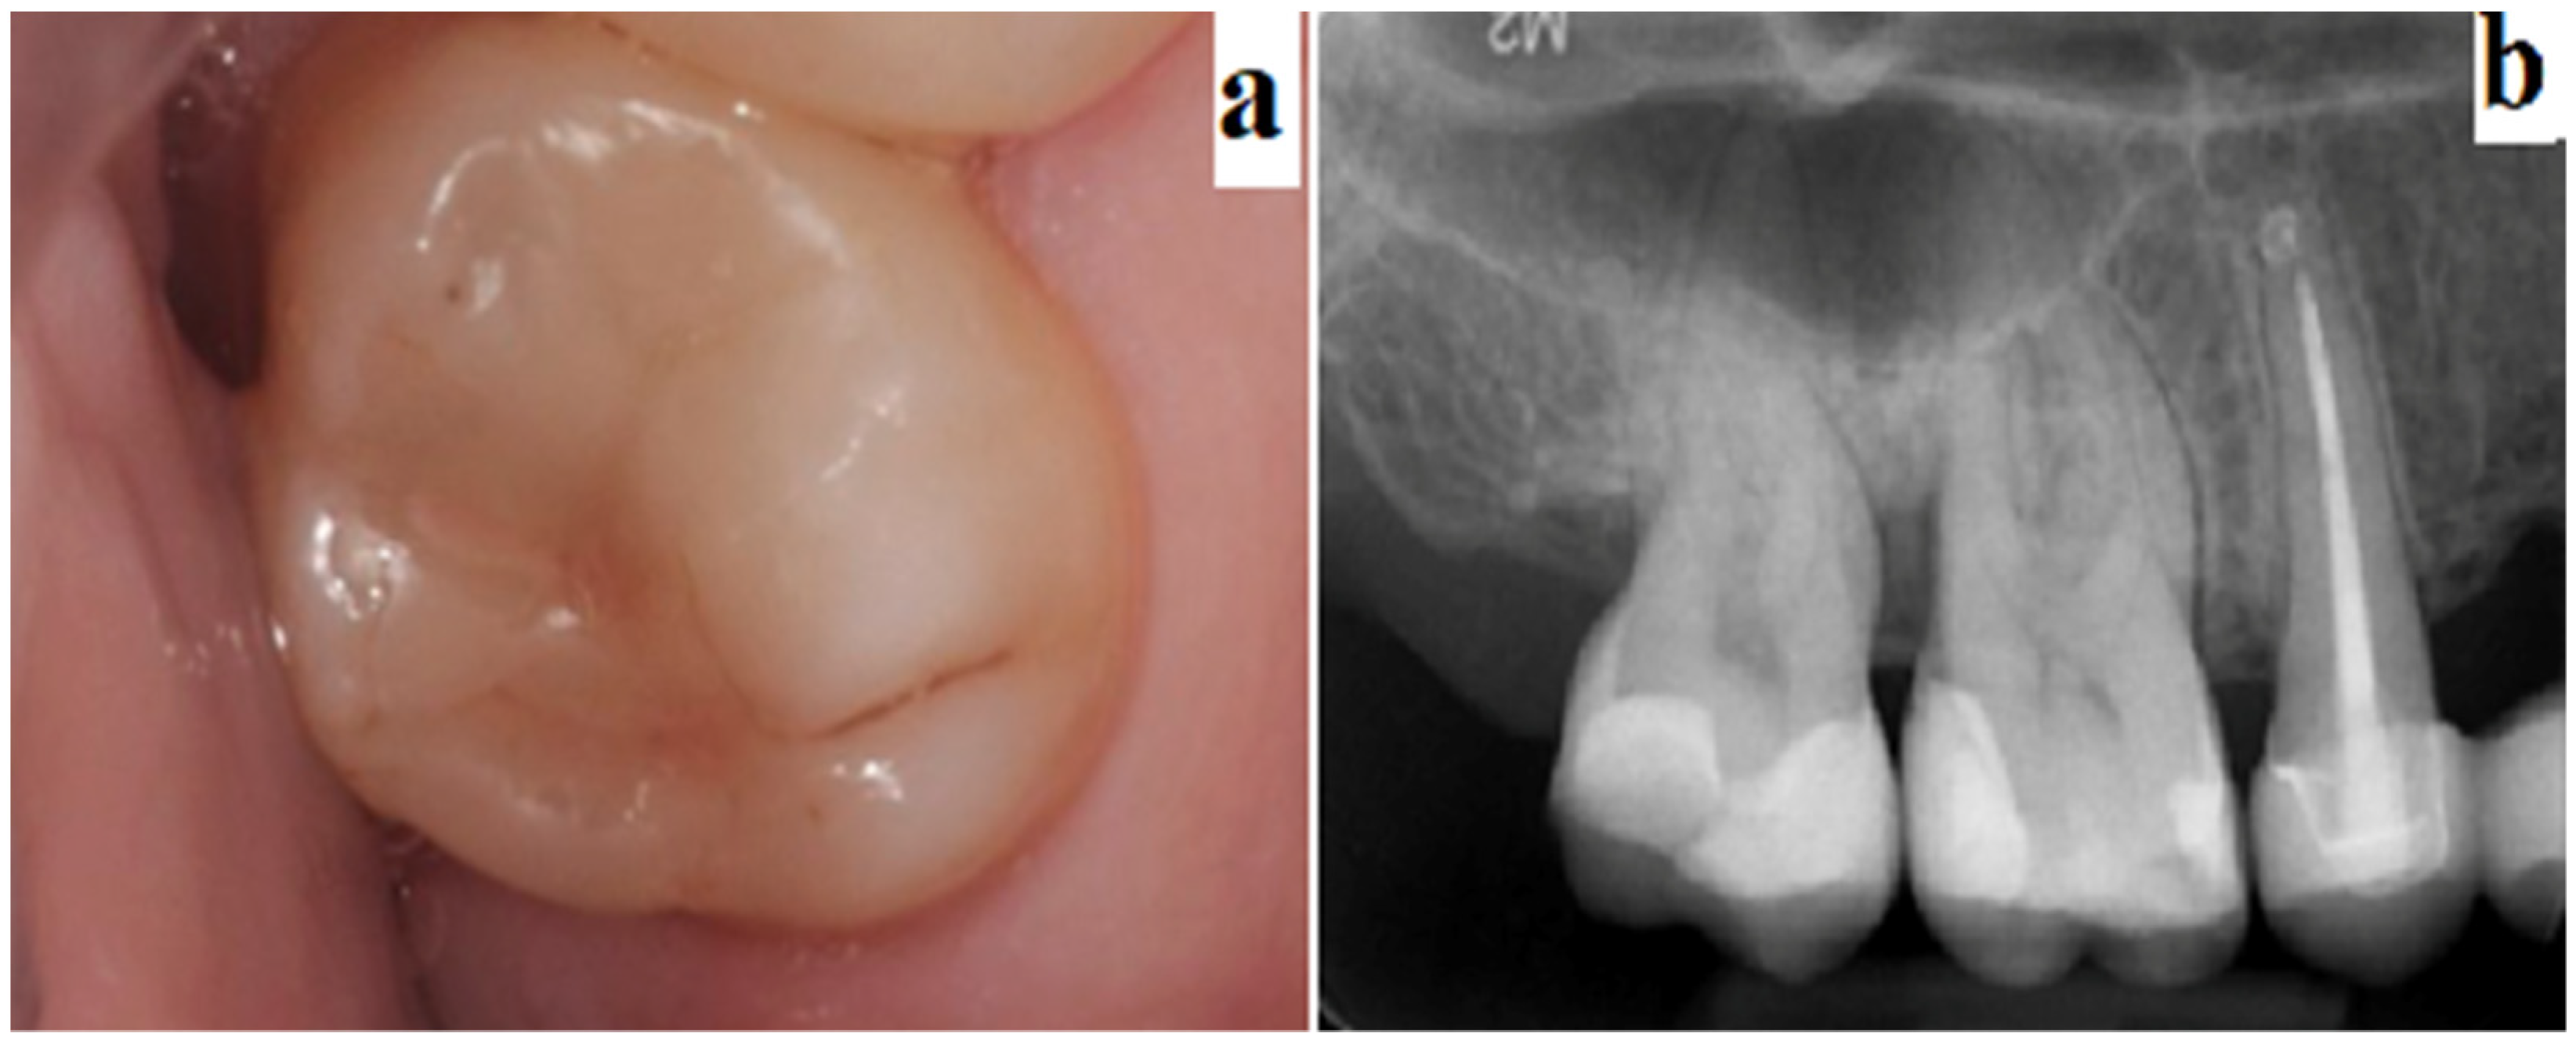

2.2. Evaluation of the Clinical Procedures of Direct/Indirect Pulp Capping